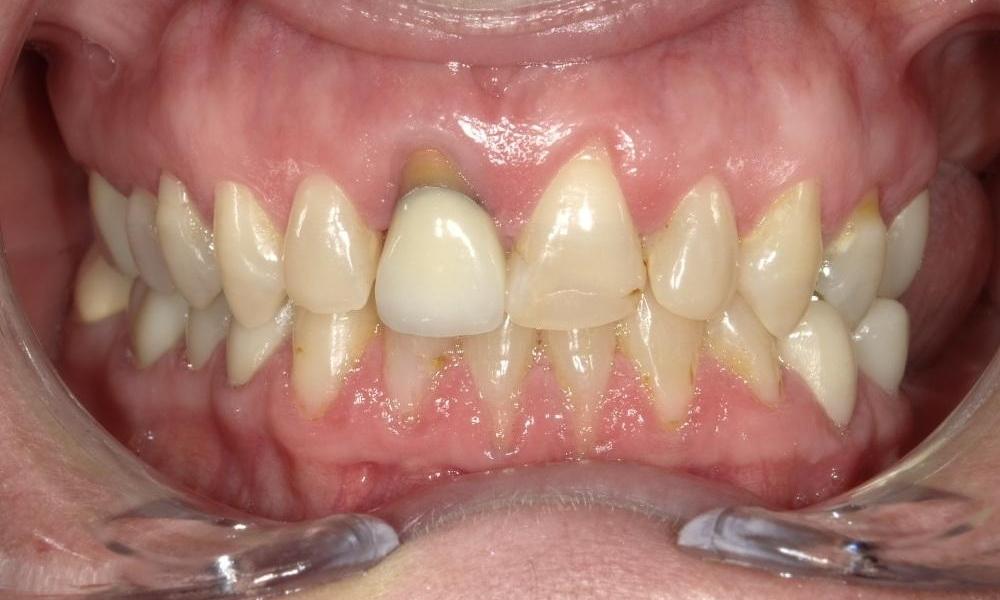

What a big difference 2 crowns can make!

Patient does not like the look of her old front crown and who could blame her.  The old crown was done a long time ago and the gum has receded, causing metal margin of the crown to show, and extensive amount of root surface exposed.  Due to having a previous root canal therapy, the tooth has gotten darker over time as well.  For cosmetic reasons, we decided to crown both front teeth to create better symmetry and enhance esthetics.  We do not use metal in our crowns so we do not need to worry about a dark crown margin showing again in the future.  At the end, we picked a crown material that has just enough translucency to look natural but not too much where the darkness of the tooth would show through.  Patient was very happy with the results and we were happy to have made a big difference in this patient's smile.